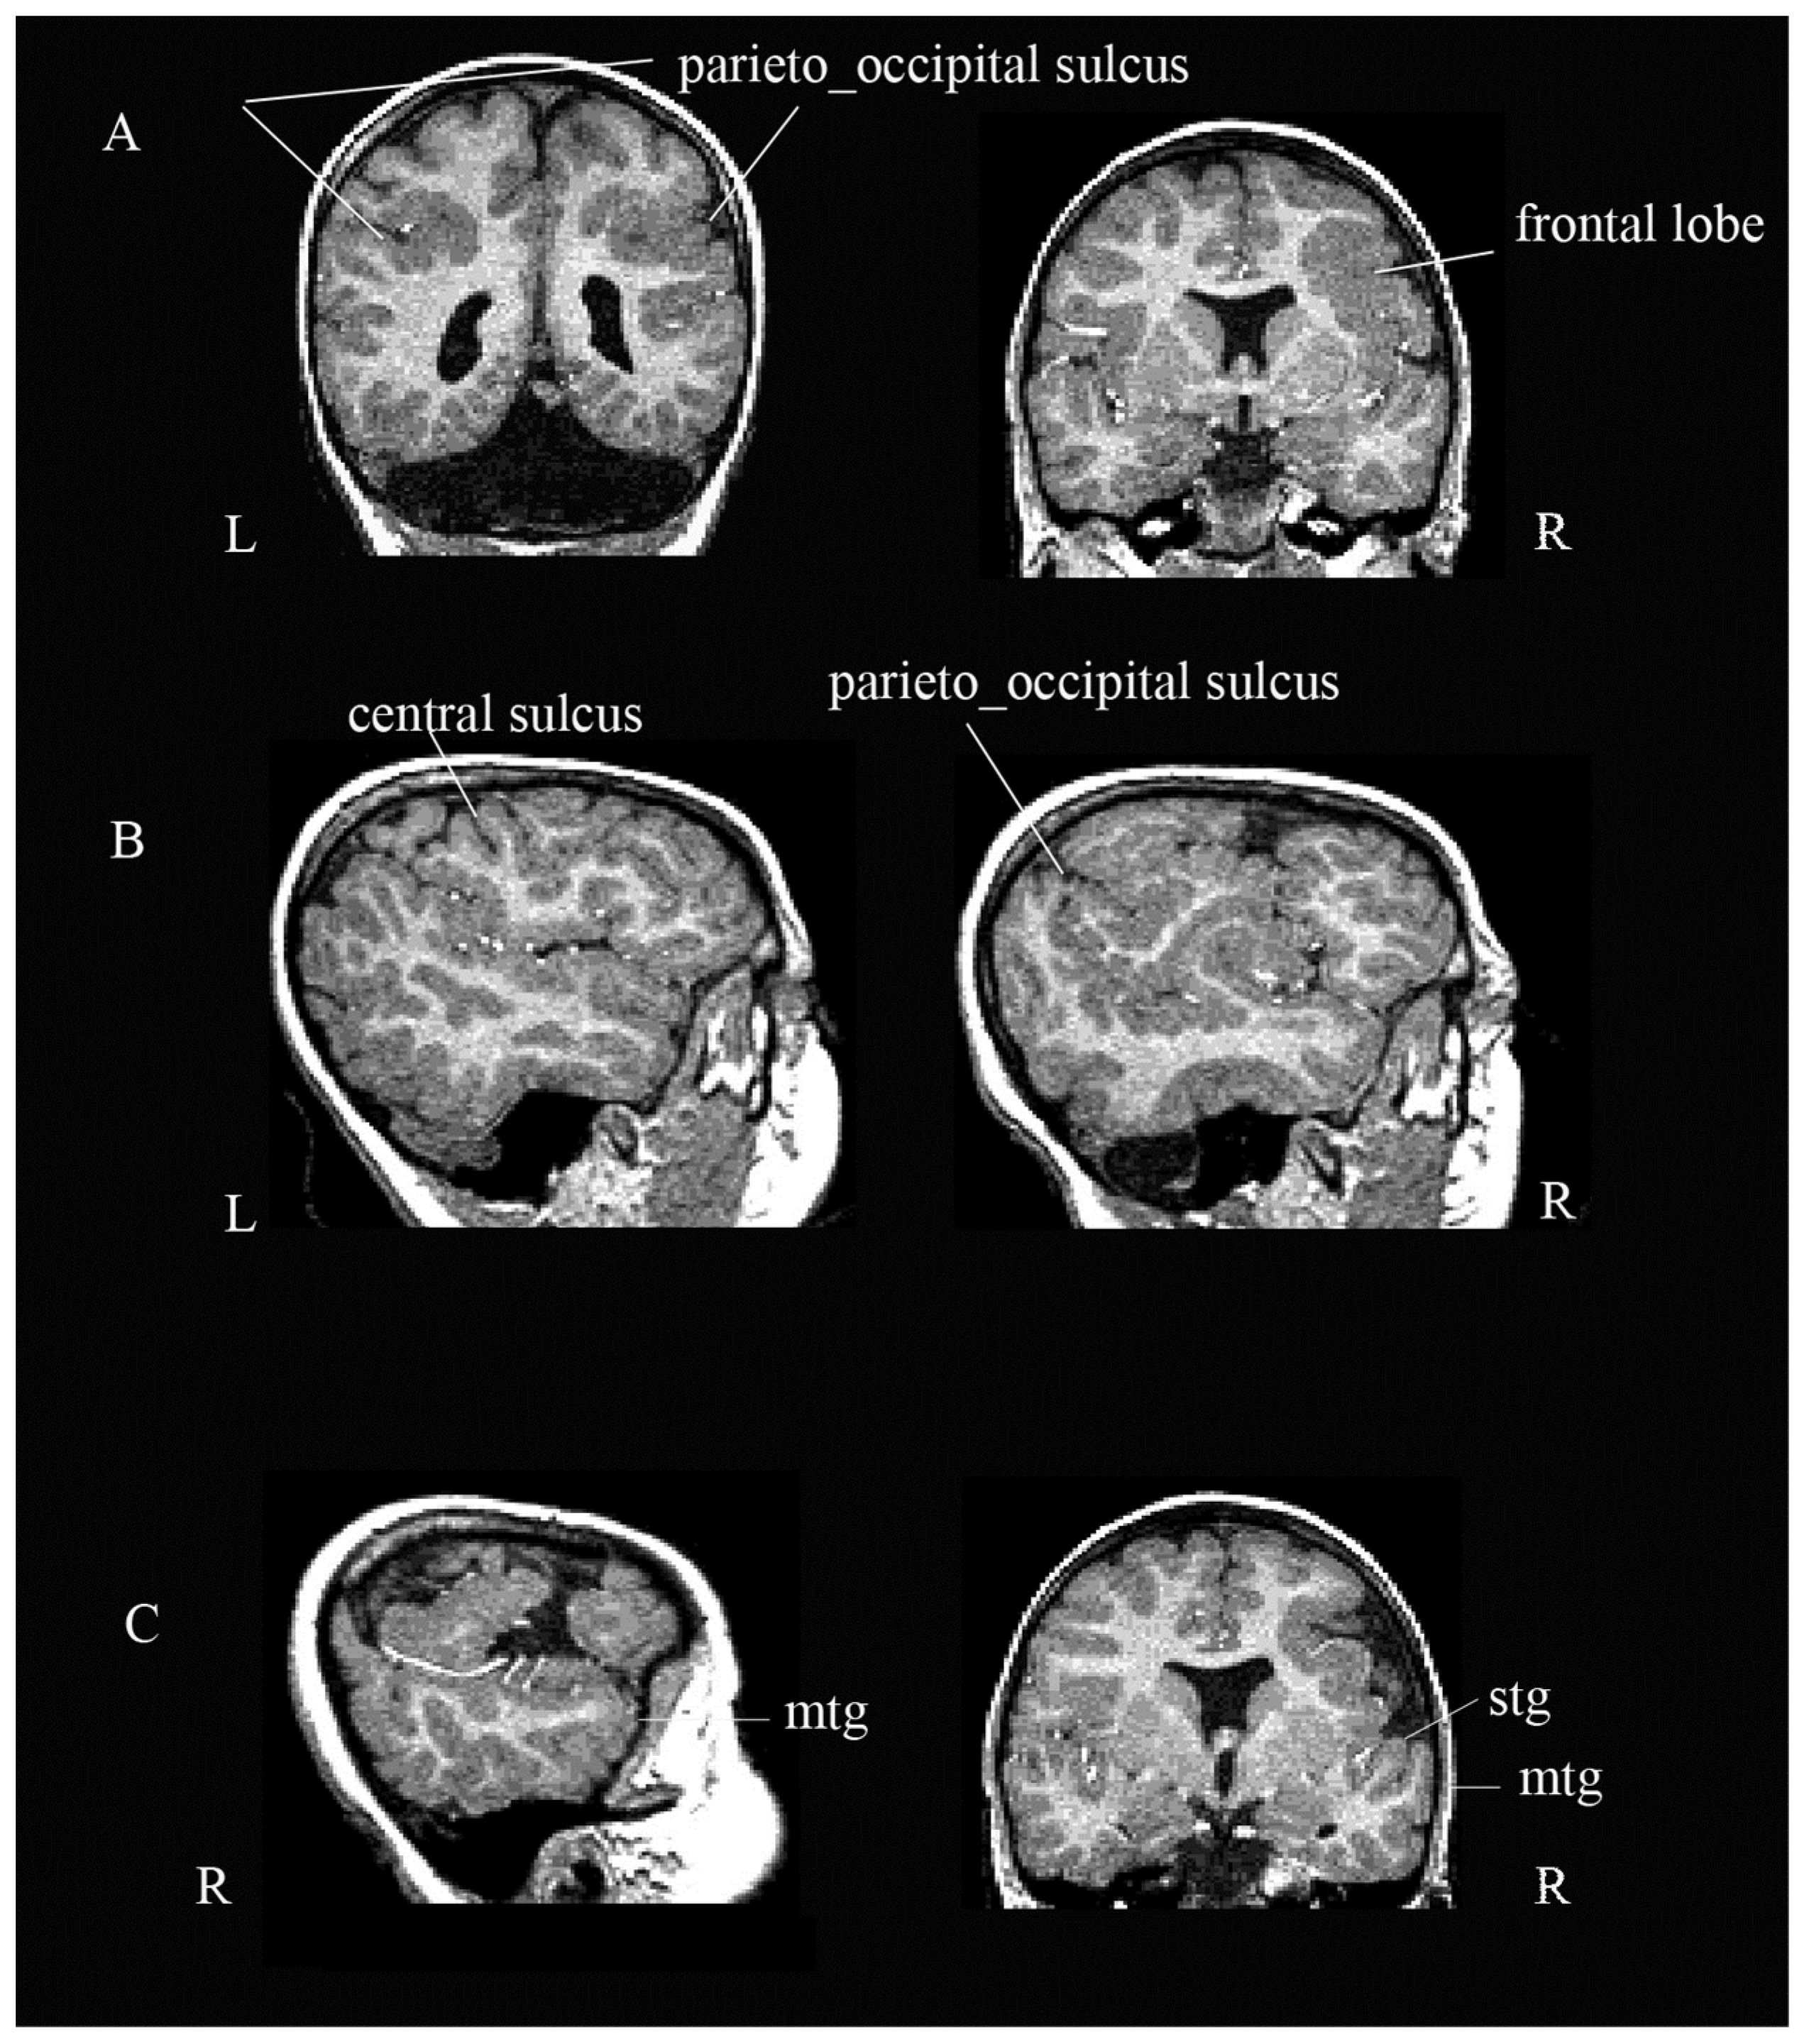

3.1. Neuroradiological Examination